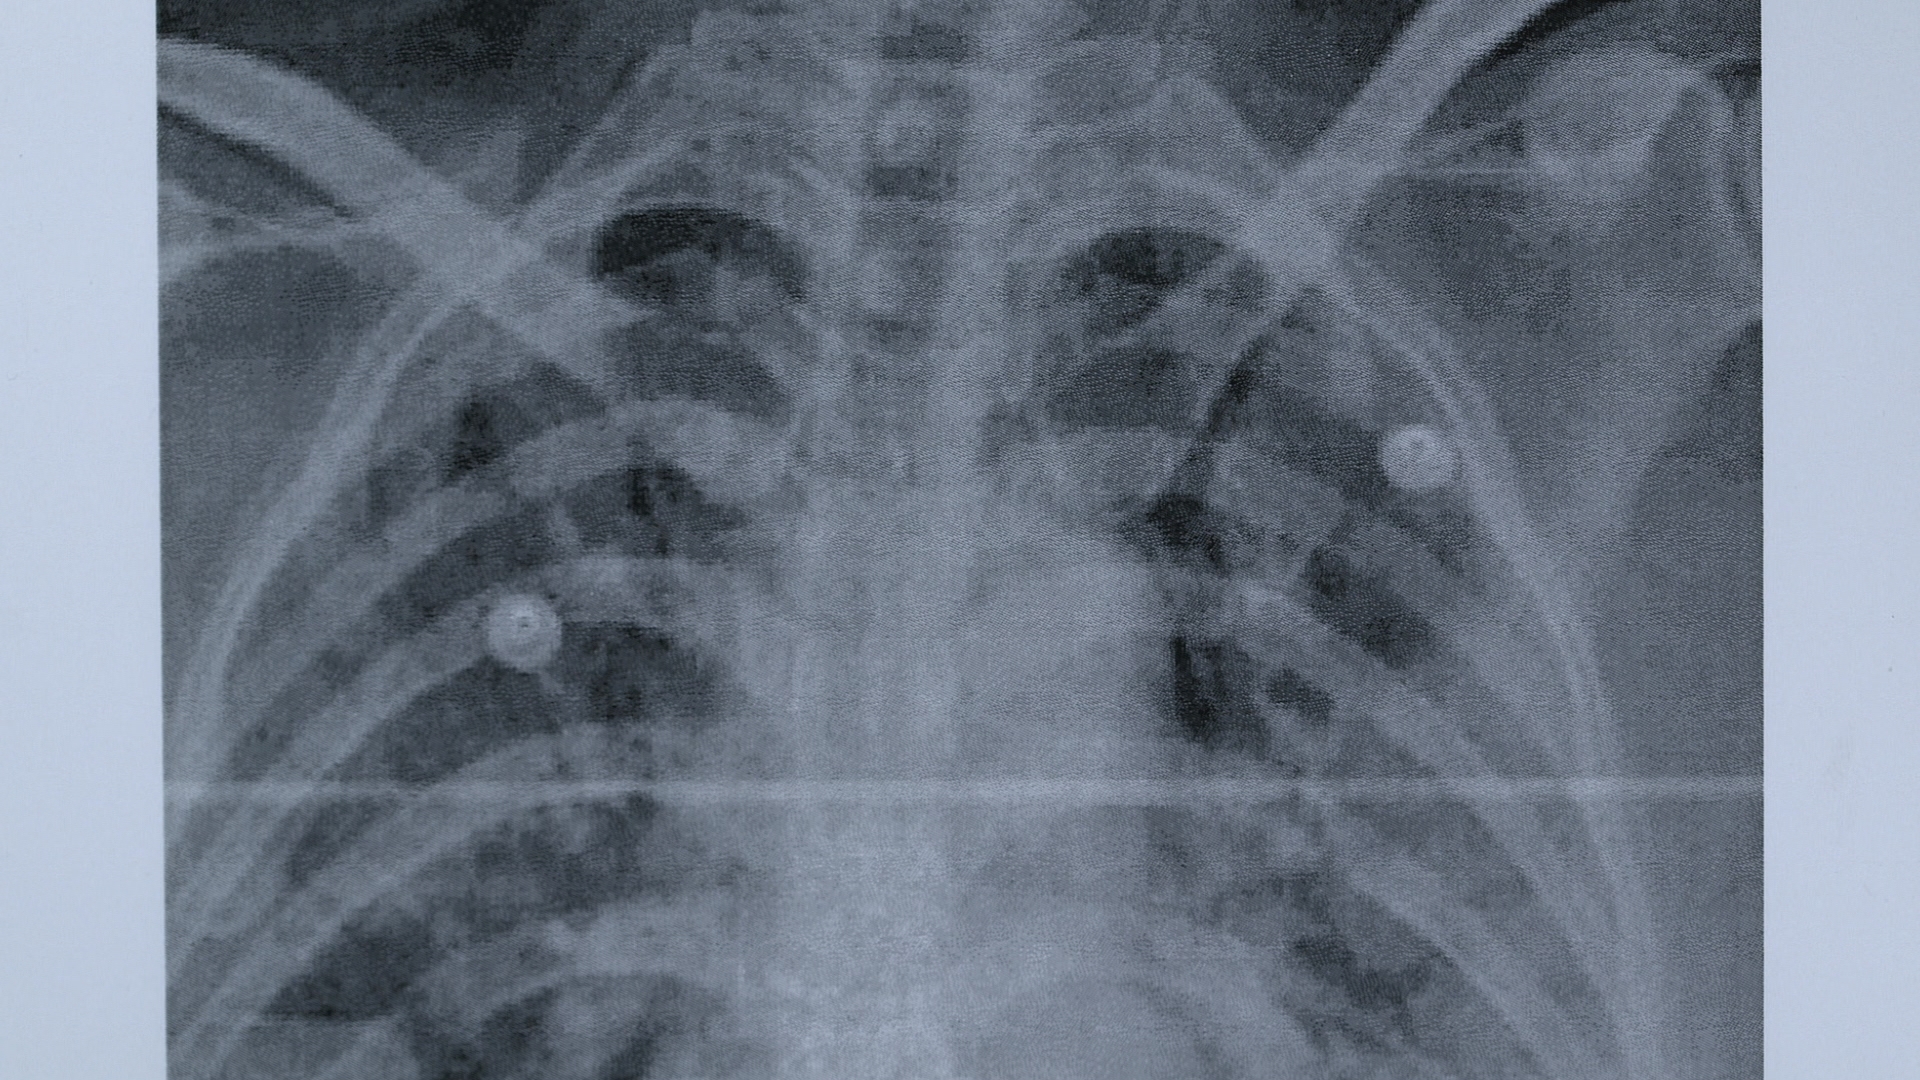

Mid-December, 2019 People begin turning up at hospitals in Wuhan with strange white spots on their lung scans. Many of the cases are traced back to the city’s Huanan Seafood Market, where a variety of live animals are sold. Whether the market is where the virus first leapt from animals to humans is unknown.